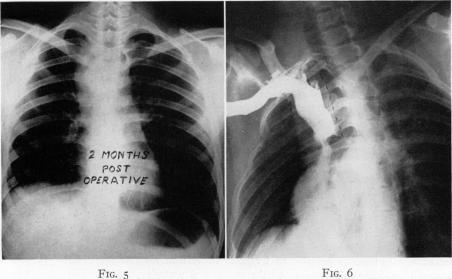

Congenital aneurysm of superior vena cava; report of one case with operative correction.

Ann Surg. 1950 Feb;131(2):259-63, illust. doi: 10.1097/00000658-195002000-00013.